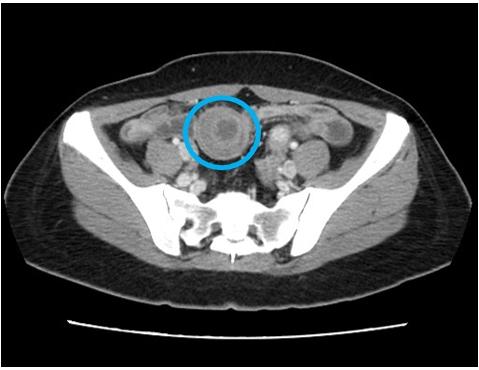

收治該患者的腸胃科黃一修醫師表示,患者的腹痛並非一般胃炎,經安排腹部電腦斷層檢查,影像顯示小腸出現「標靶徵象」,診斷為「腸套疊」。立即啟動跨科會診,將患者轉由一般外科王志浩醫師接手,進行緊急微創手術治療。

一般外科王志浩醫師隨即施行「腹腔鏡部分小腸切除術加吻合術」。術中發現,在距離迴盲瓣約150公分處,一段小腸竟然像收納望遠鏡一般,套入了另一段遠端腸道中。而這場腹內災難的元凶,是一個位於小腸黏膜下層、大小約 3x3公分的堅硬腫塊,它充當了套疊的「引導點」,導致腸道蠕動時將自身捲入。